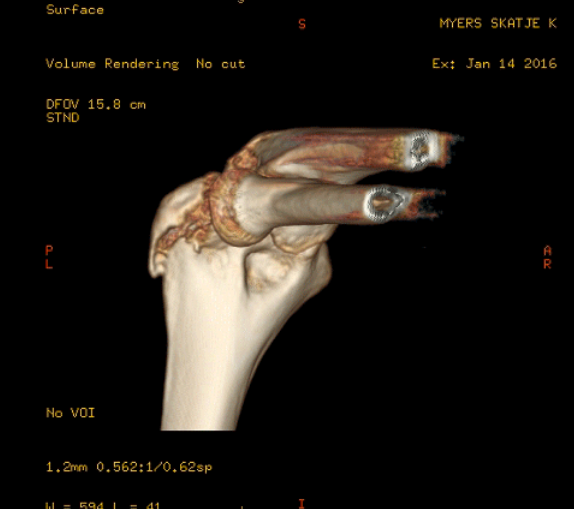

She has posted the scans of her fractured joint! Now I’m going to have to ground her, or something.

Yeah, it sucks. It’s the olecranon and it wont heal itself.. she need surgery to stabilize it.

That’s not an olecranon fracture. That looks like the lateral epicondyle of the humerus.

Wow, that looks pretty severe. With the articular surfaces involved like that, I’d be willing to bet she’ll need surgery (I’m not a doctor, but I am a radiology tech). On the plus side, they’ll make her good as new.

Orthopedic surgeon (and long-time lurker) here. Those are some really excellent CT images, great image quality. Anyway, I’m not an expert on elbows as such, but I’m pretty sure that fracture would be surgically treated (probably by percutaneus pinning) here in sweden.

Yep. Fooled by the scan. Not an olecranon fracture. Wrong side.

A good oldfashioned Xray would have done the trick here. These fancy 3-D reconstructions don’t often add much of value for elbows, and they are expensive as fuck. It either needs an operation or it doesn’t.